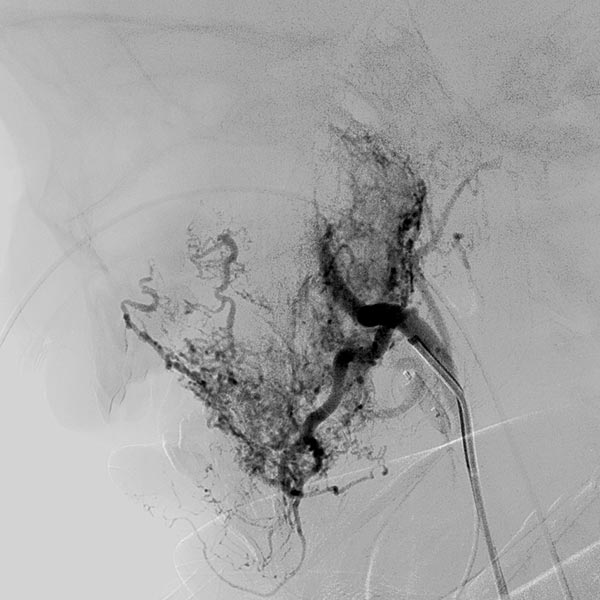

Digitale Subtraktionsangiographie (DSA) nach erster Embolisation mit Partikeln. Ein Teil des Hämangioms ist schon ausgeschaltet.

Digitale Subtraktionsangiographie (DSA) nach erneuter superselektiver Embolisation mit Partikeln über einen Mikrokatheter unter Blockung des Abstroms. Es sind jetzt gut 50 % des Hämangioms erfolgreich embolisiert.

Digitale Subtraktionsangiographie (DSA) nach Sondierung des verbliebenen, jetzt hauptsächlich noch das Hämangiom versorgenden Astes mit einem Mikrokatheter.

Während der superselektiven Partikelembolisation über den Mikrokatheter nach Blockung des venösen Abstroms (150 Mikron-Partikel) sind die Partikel zu erkennen als flau kontrastiertes Areal.

In der Kontrollangiographie über den Führungskatheter ist das Hämangiom jetzt praktisch nicht mehr perfundiert. Es zeigt sich das Bild des entlaubten Baums.

Die Übersichtsangiographie über die Arteria carotis communis nach Entfernung des venösen Blockballons zeigt ein praktisch komplett devaskularisiertes Hämangiom. Die intracerebrale Zirkulation ist unauffällig.